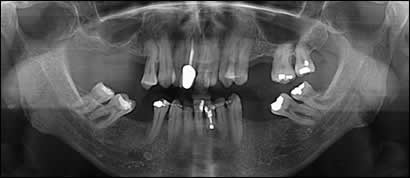

Fig 1: A 63 year old male presented with several missing teeth. The narrow and asymmetrical palate was an obstacle to several prosthetic options. A fixed porcelain bridge supported by dental implants was eventually chosen to restore form and function to the upper dental arch.

Fig 2: The upper teeth were removed and the extraction sites were grafted with bone to serve as a foundation for implant placement.